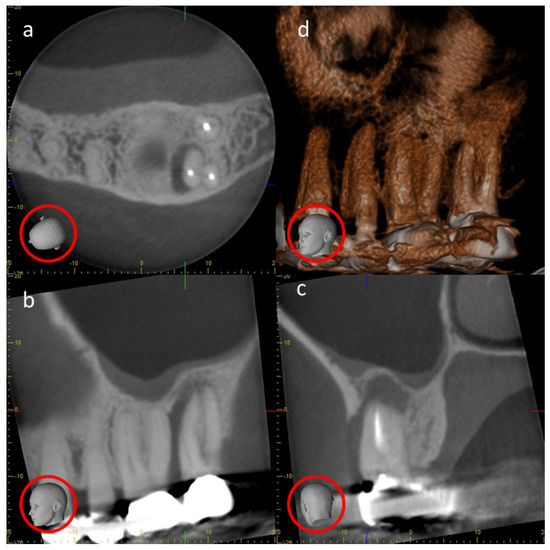

4.2. Metal Artifacts and Use of Metal Artifact Reduction Software

- Kim, Y.H.; Lee, C.; Han, S.S.; Jeon, K.J.; Choi, Y.J.; Lee, A. Quantitative analysis of metal artifact reduction using the auto-edge counting method in cone-beam computed tomography. Sci. Rep. 2020, 10, 8872. [Google Scholar] [CrossRef] [PubMed]